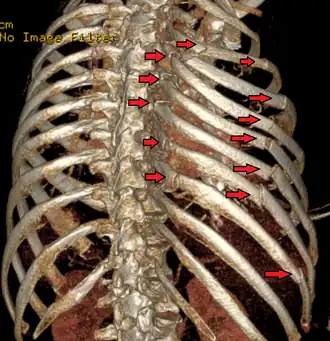

| Uma reconstrução 3D de uma tomografia computadorizada mostrando um tórax instável. As setas marcam as fraturas das costelas. | |

O tórax instável normalmente ocorre quando três ou mais costelas adjacentes são fraturadas em dois ou mais locais, permitindo que esse segmento da parede torácica se desloque e se mova independentemente do resto da parede torácica. O tórax instável também pode ocorrer quando as costelas são fraturadas proximalmente em conjunto com a desarticulação das cartilagens costais distalmente. Para que a condição ocorra, geralmente deve haver uma força significativa aplicada sobre uma grande superfície do tórax para criar múltiplas fraturas de costelas anteriores e posteriores. Lesões por capotamento e esmagamento geralmente quebram as costelas em apenas um ponto, enquanto para que o tórax instável ocorra é necessário um impacto significativo, quebrando as costelas em dois ou mais lugares.[15] Isso pode ser causado por acidentes violentos, como as colisões de veículos mencionadas acima ou quedas significativas. Nos idosos, pode ser causada pela deterioração óssea, embora rara. Em crianças, a maioria das lesões torácicas instáveis resulta de traumas comuns de força contundente ou doenças ósseas metabólicas, incluindo um grupo de doenças genéticas conhecidas como osteogênese imperfeita.[16]

O diagnóstico é feito por exame físico realizado por um médico. O diagnóstico pode ser auxiliado ou confirmado pelo uso de imagens médicas com radiografia simples ou tomografia computadorizada. Movimentos paradoxais de segmentos manguais. Crepitação e sensibilidade perto de costelas fraturadas.